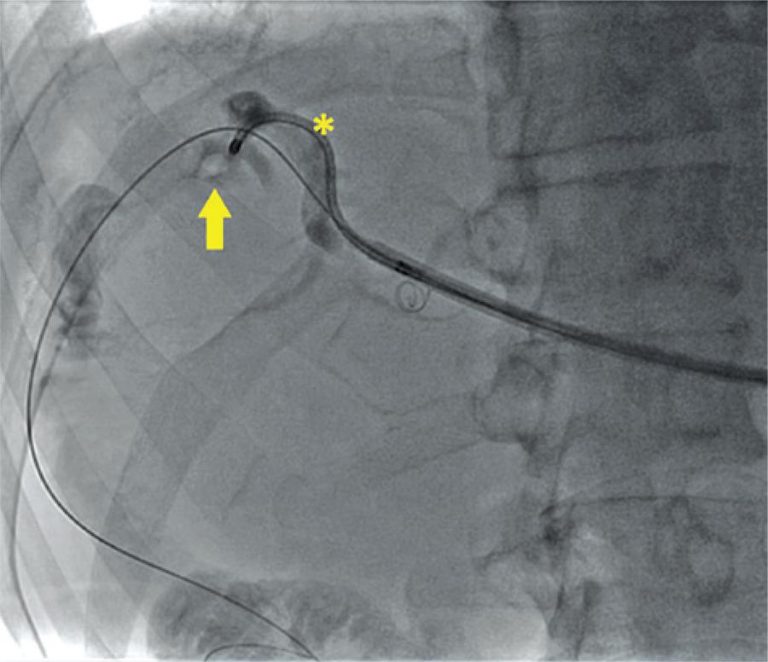

A maioria das doenças litiásicas das vias biliares necessita de tratamento cirúrgico. No entanto, em casos especiais, que não permitem o acesso tradicional das vias biliares por via endoscópica, a abordagem multidisciplinar com técnica híbrida, que utiliza instrumentais endourológicos, apresenta-se como uma opção no tratamento. Relatamos aqui o caso de um paciente com litíase de via biliar complexa com múltiplas abordagens prévias, sem sucesso no tratamento com métodos convencionais, resolvido com abordagem híbrida com tecnologia endourológica. Realizamos uma extensa busca […]